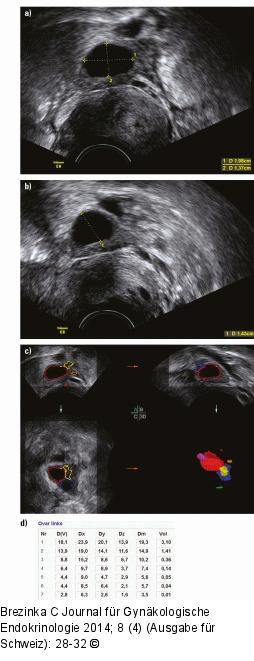

Abbildung 4a-d: Follikelmessung 14. Zyklustag bei Clomifen-Stimulation: (a) Zunächst wird der Follikel in der maximalen Größe dargestellt und gemessen, (b) in der Folge wird der Schallkopf 90° gedreht und eine weitere Messung durchgeführt. (c) Die Sono-AVC-Messung zeigt den größten Follikel in Rot an. (d) Die Messung zeigt zuerst den auf die elliptische Form des Follikels bezogenen Follikeldurchmesser D(V), dann die Messung in 3 Ebenen, wie sie das System vornimmt, und dann den Mittelwert aus Dx, Dy und Dz. Der letzte Wert gibt das errechnete Volumen in Millilitern an. |

14. Zyklustag bei Clomifen-Stimulation: (a) Zunächst wird der Follikel in der maximalen Größe dargestellt und gemessen, (b) in der Folge wird der Schallkopf 90° gedreht und eine weitere Messung durchgeführt. (c) Die Sono-AVC-Messung zeigt den größten Follikel in Rot an. (d) Die Messung zeigt zuerst den auf die elliptische Form des Follikels bezogenen Follikeldurchmesser D(V), dann die Messung in 3 Ebenen, wie sie das System vornimmt, und dann den Mittelwert aus Dx, Dy und Dz. Der letzte Wert gibt das errechnete Volumen in Millilitern an. |